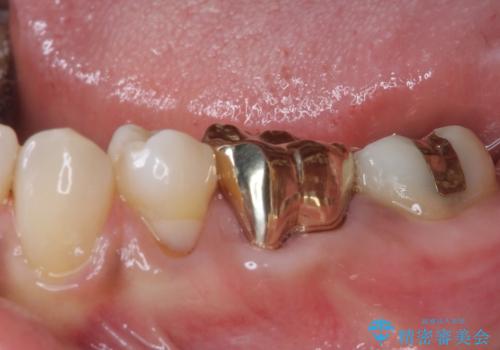

ゴールドは「白い歯」ではありませんが、銀歯の金属色とは異なり、非常にきれいな色合いが特徴です。

もちろん、適合が極めて良いという圧倒的メリットもゴールドクラウンやゴールドインレーの特徴です。